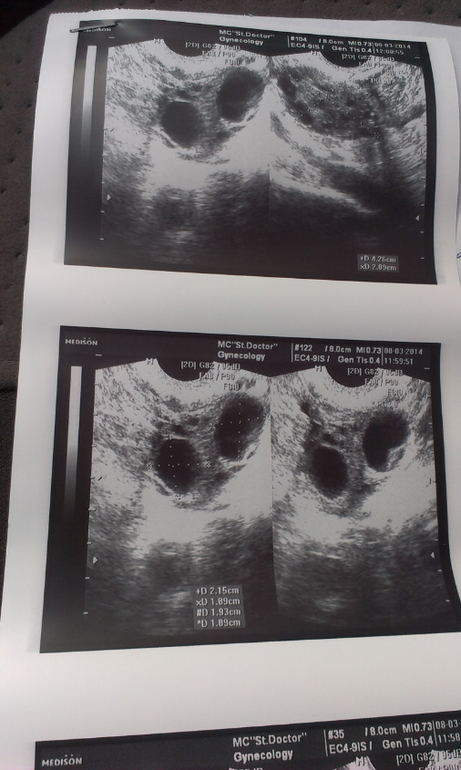

И теперь пребываю в шоке. Правый яичник не изменился, а вот левый. 2!!! образования (20мм и 19мм) , узист незнает желтое тело это или нет. (типо если бы делали узи с самого начала у нее она бы сказала) и умеренное количество жидкости в позадиматочном пространстве. Помогите понять, а то голова ща лопнет

Фото прилагаю.